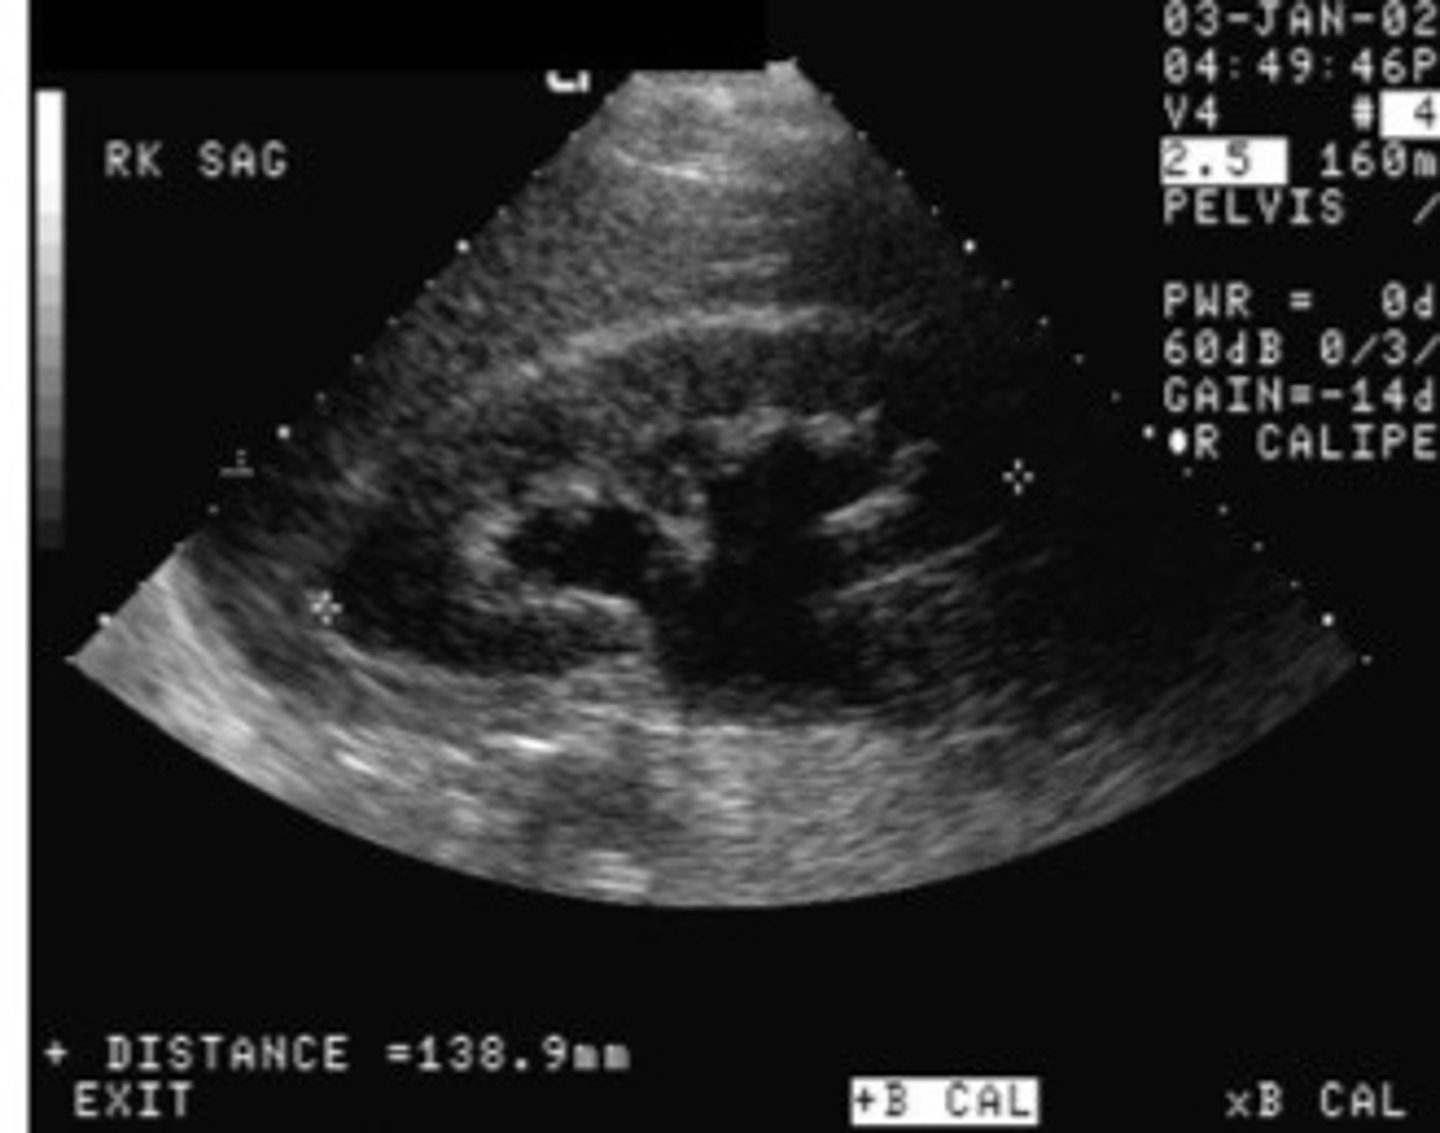

Grade 3 hydro

What does this image show